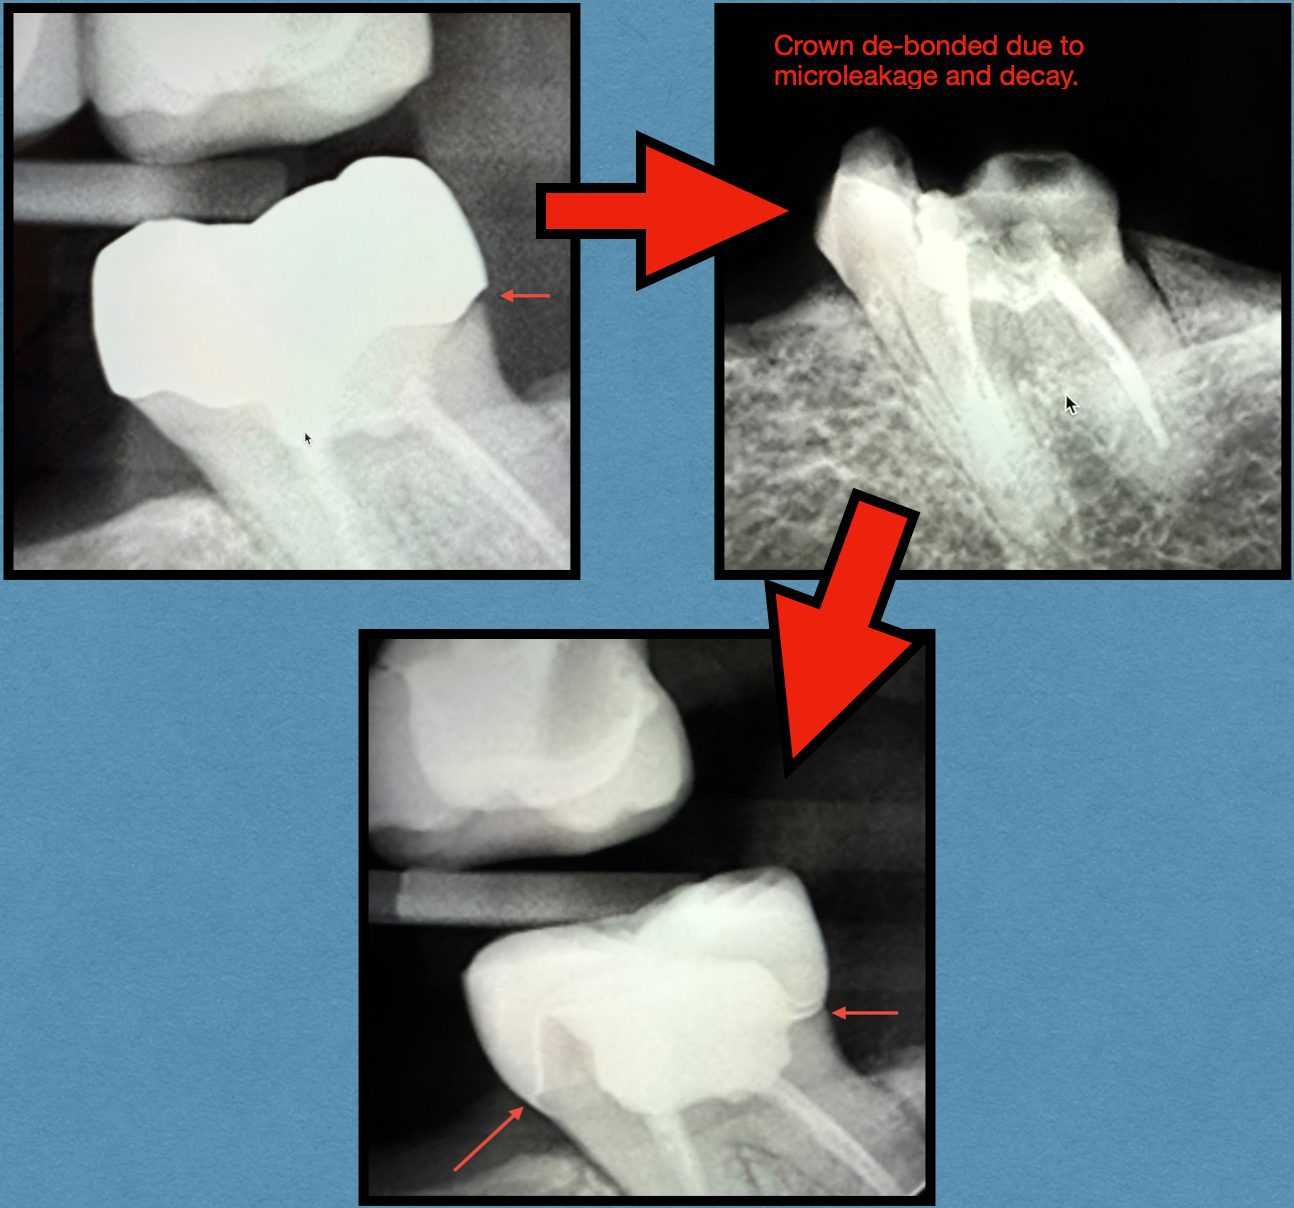

The images below show a perfect example:

- Before: An older crown looked intact on the surface, but x-rays revealed leakage around the margins. This allowed bacteria to slip underneath, leading to decay and ultimately loosening the crown.

- During Treatment: Once the compromised crown was removed, the extent of the damage became clear. Decay had undermined the underlying tooth structure, requiring careful cleaning and preparation.

- After: The tooth was rebuilt and restored with a new, custom crown. Notice how the new restoration forms a seamless, tight bond with the natural tooth. This strong seal not only restores appearance and function but also protects against future leakage and decay.